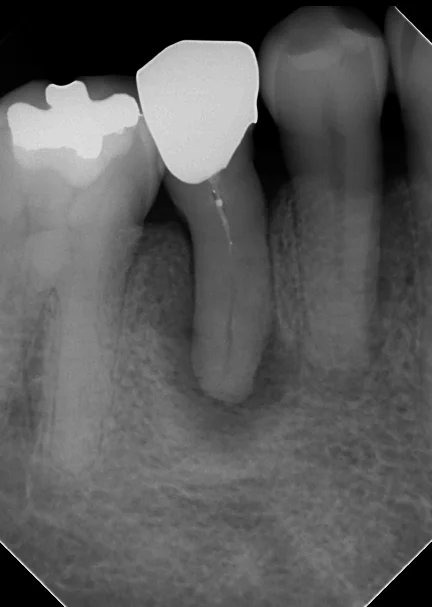

詰め終わった直後のレントゲンがこちらです。

閉鎖根管の治療には根気が必要|坂寄歯科医院(取手市藤代) - 画像3

根の先の方までしっかりと綺麗に詰まっています。

根の先の膿の部分は処置スタートから1ヵ月しか経過していない為、全く変化がない状態です。

根の先の骨は数年単位でじりじりと溶かされていきますので、感染源が無くなったからと言って、すぐに骨が再生するわけではありません。

少なくとも半年~1年程度しっかりと経過を診てみないと本当に治療が成功したかどうかは分からないのが現実です。